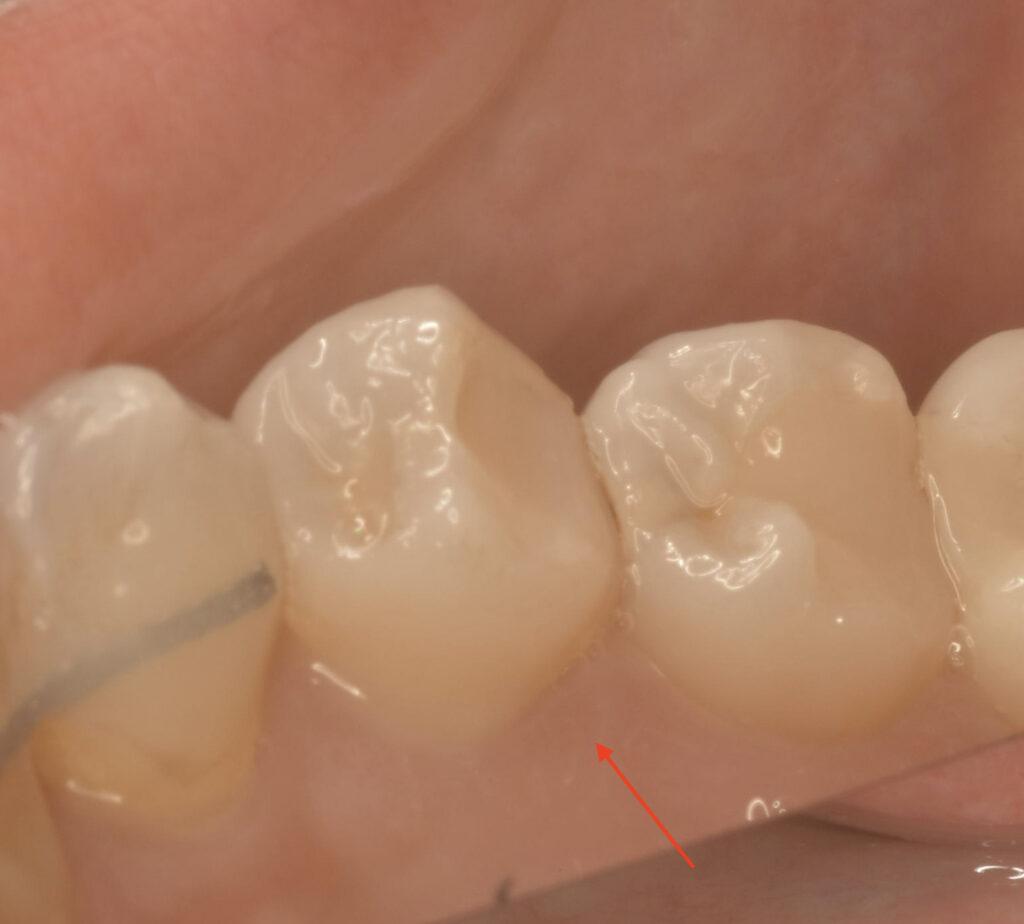

口腔内を見た状態 キレイにレジンが詰められていますね

上の写真は舌側(内側)からみたところ